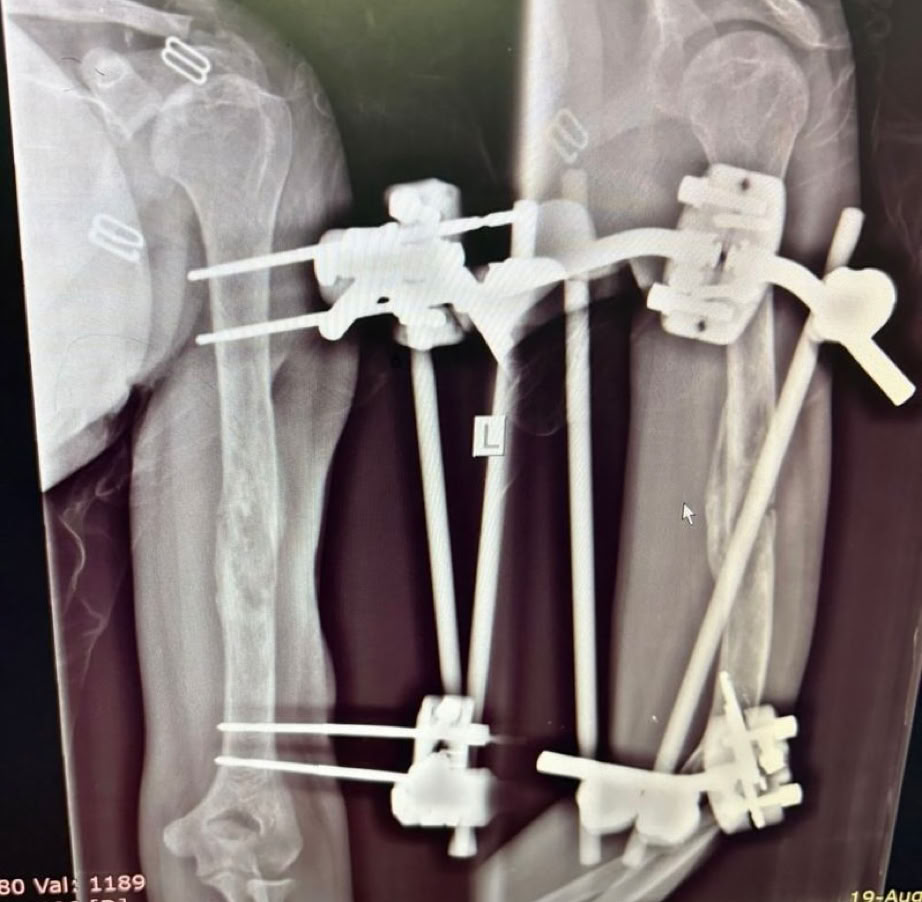

Nos encontramos dos casos de rodillas flotantes que pudimos resolver y casos de retardo de consolidación e infecciones de intervenciones previas. Igualmente las osteomielitis hematógenas y las sécales de la diabetes ocupa gran parte de la actividad de consultas de sala de curas y de las sesiones quirúrgicas.

A partir del lunes y tras la oración de bienvenida al inicio de la jornada en la que nos fuimos presentando todos los componentes de la expedición, las tareas asignadas se fueron distribuyendo entre la consulta, las dos salas de Curas y los dos quirófanos, que además se han mantenido activos todos los días de la semana en turnos de mañana y tarde con cirugías complejas en ambos. Esto nos ha permitido por ejemplo abordar principalmente enclavados de fémures y tibias y también casos de luxaciones inveteradas de hombro y de tobillo.

Hemos intervenido el total 29 pacientes programados, no siendo necesario llevar a cabo ninguna intervención de urgencias. Los casos más complejos se  fueron discutiendo al final de la jornada de trabajo para encontrar la manera más adecuada de abordarlos a nuestro medio y al entorno.

Como en expediciones anteriores, las complicaciones de cirugías previas en otros centros, la demora de los tratamientos por el empleo de la medicina tradicional (masajes) mencionada antes, y la elevada tasa de infecciones tanto hematógenas como secundarias a diabetes mal controlada o sin tratamiento, han ocupado gran parte de nuestro trabajo.

Los accidentes de tráfico, o de moto en su casi totalidad, como mecanismo de producción nos da una idea de la alta complejidad de los pacientes que han ocupado nuestra labor diaria, labor que hemos llevado a cabo mano a mano con el equipo local, al que vemos en cada expedición tener una mayor autonomía, experiencia técnica y profesionalidad. Hemos echado de menos al  Dr. Yannick que se ha marchado a Francia para hacer su especialización, confiemos en que vuelva. Si hemos podido compartir cirugías y consultas con los doctores Emmanuel y Ármel viendo como van aumentando su experiencia.